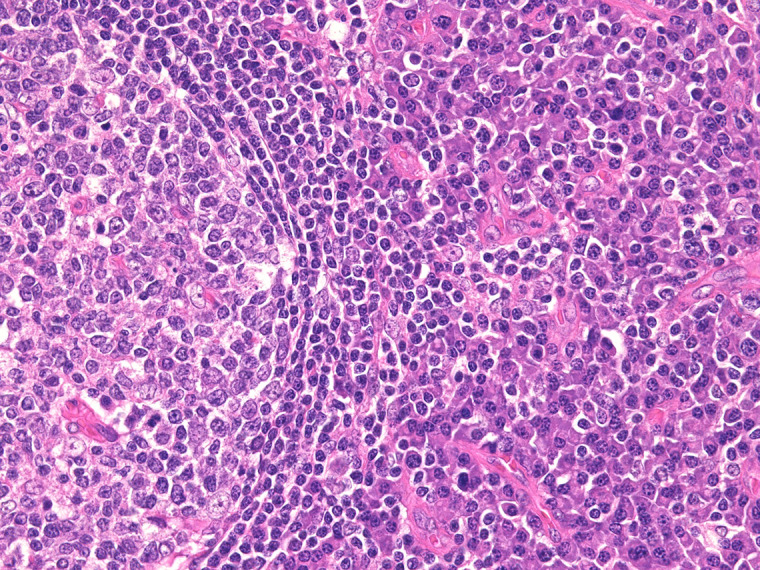

Abstract Image